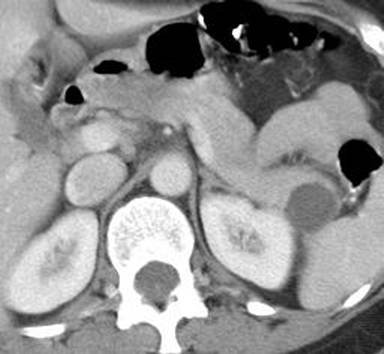

A 45-year-old female was referred for evaluation of an incidental cystic lesion in the tail of the pancreas (Figure 1). Initial EUS examination revealed a 29x18 mm unilocular cyst in the tail of the pancreas (Figure 2). EUS-FNA yielded a clear watery fluid with a CEA level of 7.4 ng/mL and an elevated amylase level of 158,464 IU/L. Cytology revealed rare macrophages with debris; a mucicarmine stain was negative. The results were felt to be most consistent with a pseudocyst; however, there was no history of pancreatitis. Surveillance EUS was recommended and was performed one year later. This exam revealed a 36x30 mm anechoic cyst with a very small septation. The cyst aspirate was clear but slightly viscous, with an elevated CEA level of 457 ng/mL. Cytology again revealed macrophages and degenerated cells with a negative mucicarmine stain. A mucinous cystic neoplasm was suspected, and the patient underwent uneventful laparoscopic resection. Final surgical pathology revealed a mucinous cystic neoplasm with focal borderline features (Figure 3).

Figure 1. CT scan of unilocular cyst within the tail of the pancreas. (Patient #1). |